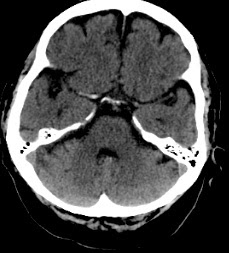

Varón de 73 años que ingresa en Urgencias con un cuadro de habla incoherente y hemiparesia derecha de aparición brusca

TC al ingreso